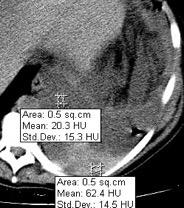

Hemorrágica………….30-70 UH

Extravasación iv. con sangrado activo……….>90 UH

“Simpático”………….,,,,<15 UH

Durso AM et al. Penetrating Thoracic Injury. Radiol Clin N Am 2015.

Urogénico……………….< 15 UH

Entérico.. ………………+/- 15UH

Biliar, Quiloso……………..<0 UH

Abramowitz1 Y et al. Pleural Effusion: Characterization with CT Attenuation Values and CT Appearance .AJR 2008